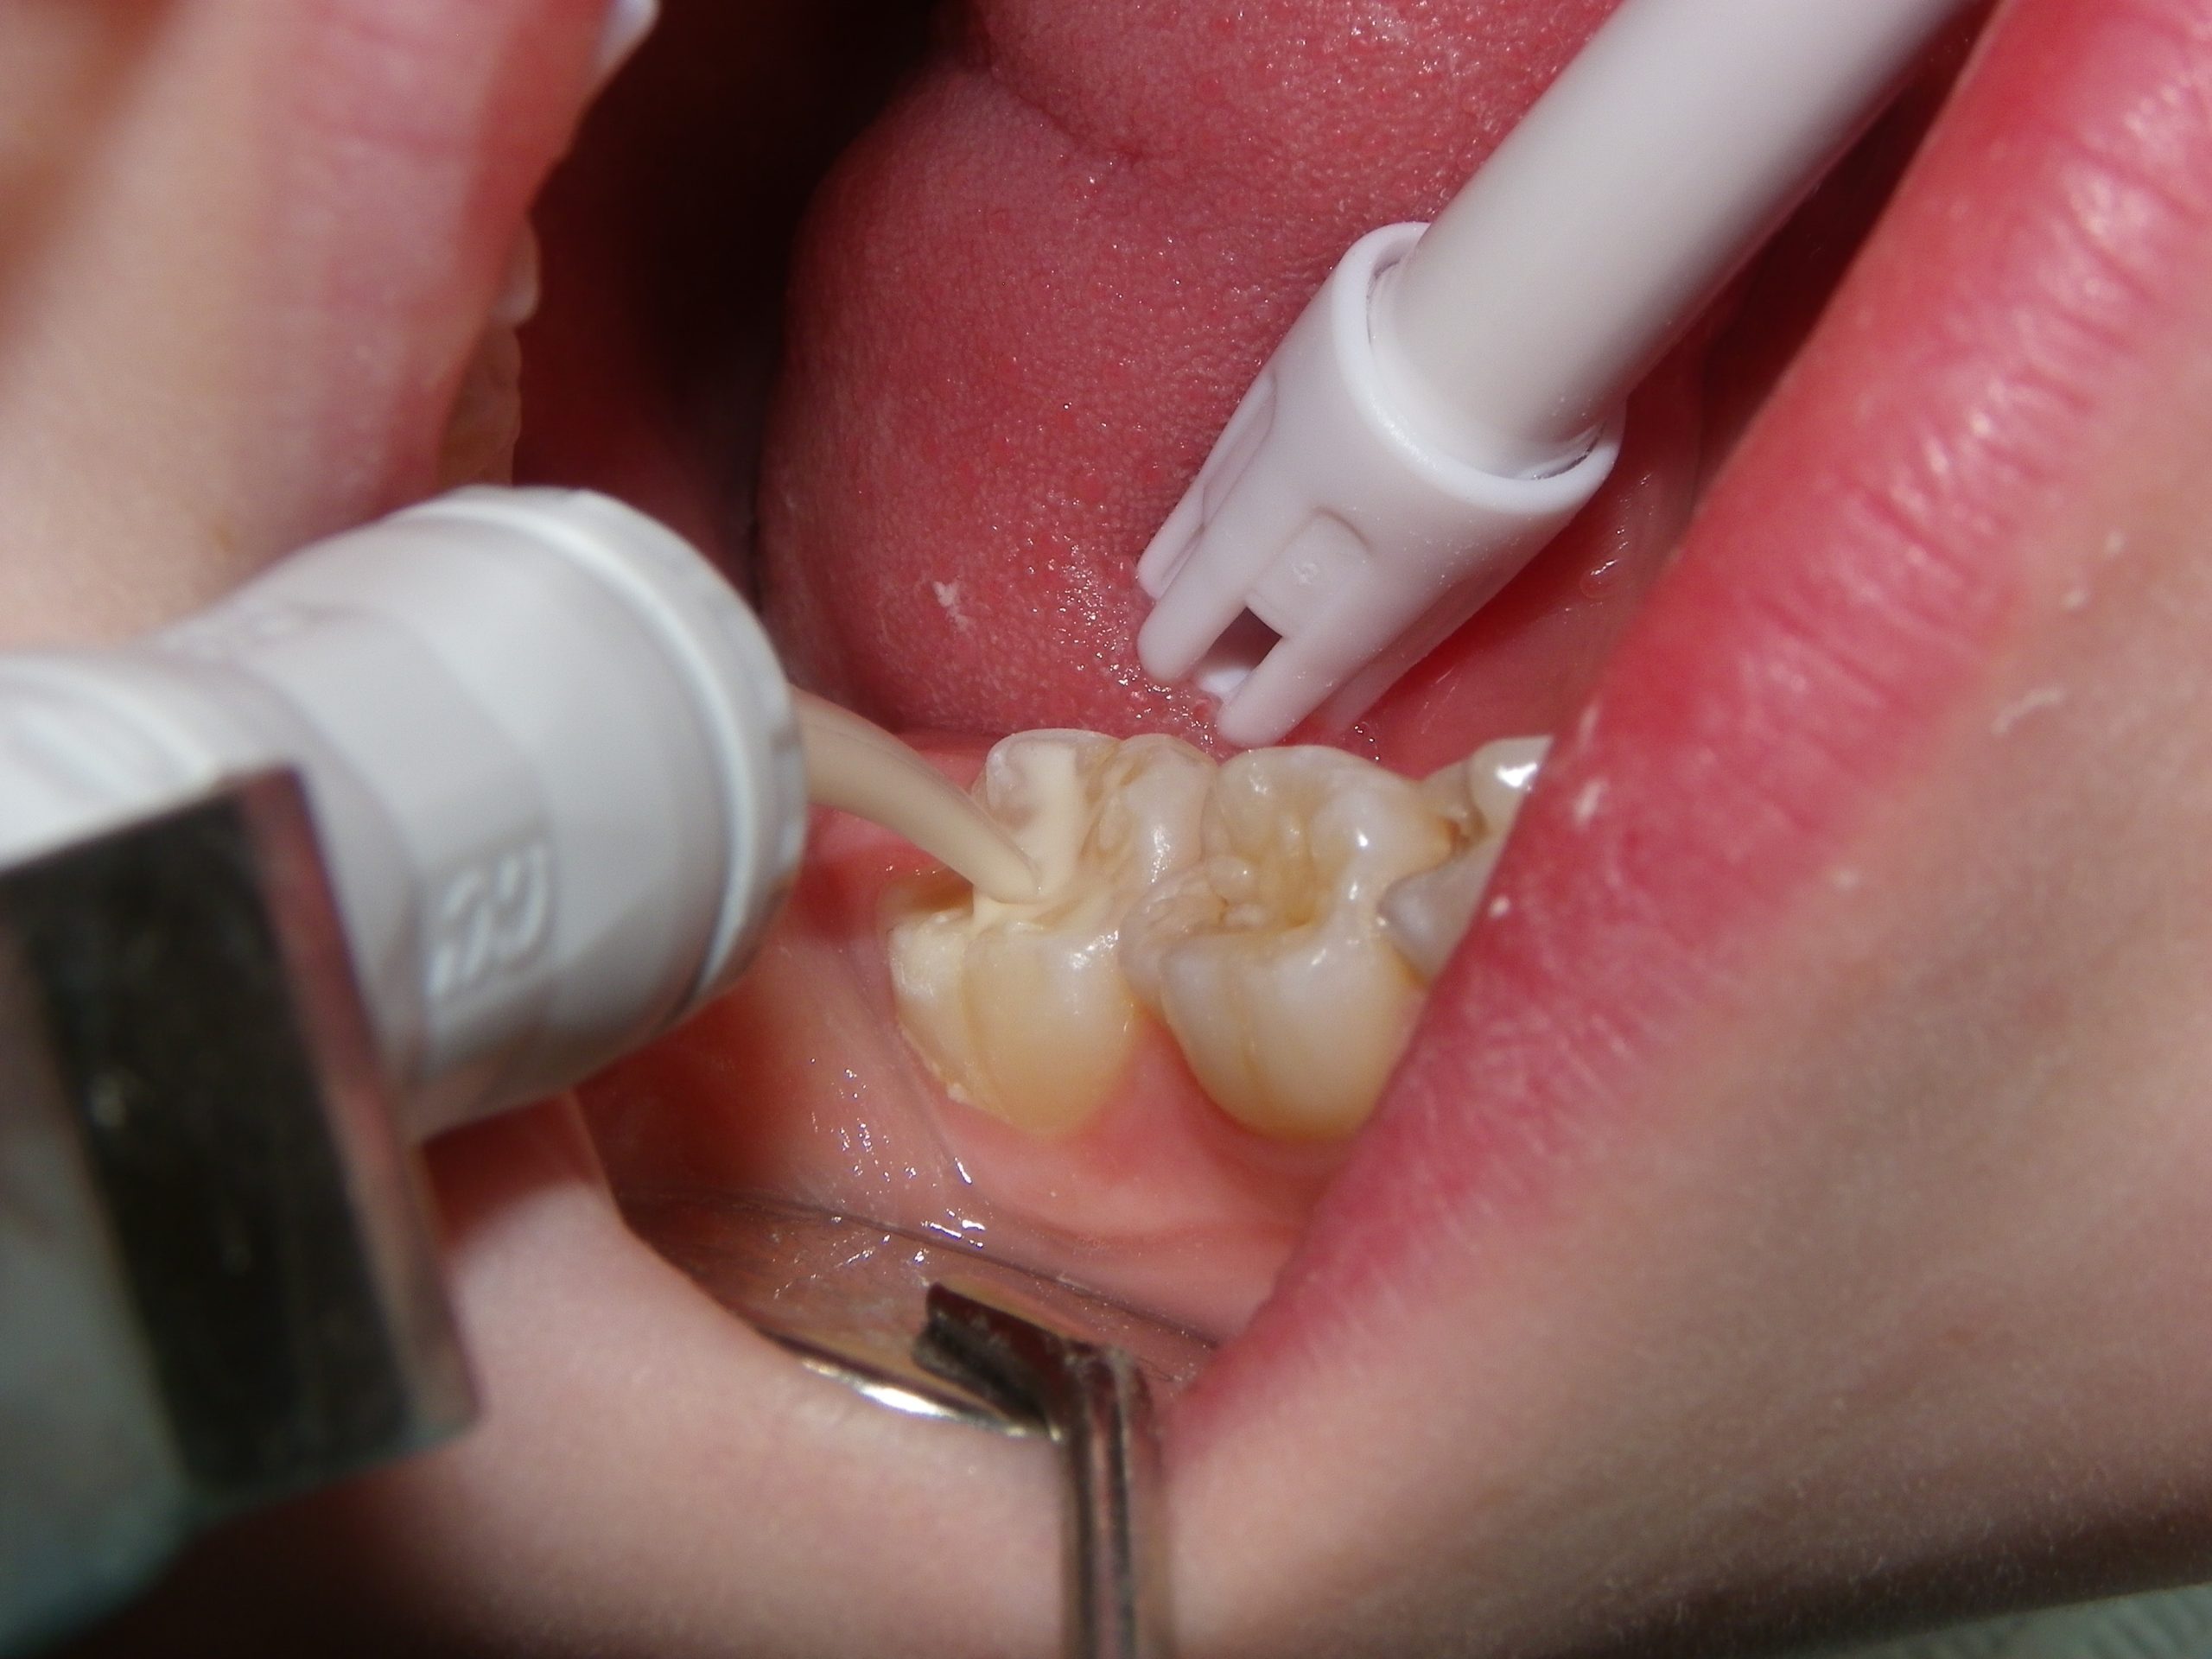

This quick photo series shows the step-by-step process of placing a sealant onto the grooves of an adult molar of a six-year-old. First, air abrasion is used to mechanically remove any loose surface debris or contaminants. Secondly, an acid gel is applied to the surface to be sealed. Finally, a sealant is applied to the surface and allowed to set. For the sharp-eyed, the sealant used was GC Fuji Triage, a glass ionomer sealant that while not as wear-resistant as the more commonly used resin sealants, is more moisture-friendly (ie: contamination resistant) and releases fluoride. The fluoride release allows the underlying enamel to be strengthened over time, making it more decay-resistant for the future.